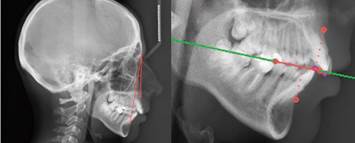

Determinación de la clase esquelética

La toma de las telerradiografías laterales de cráneo se realizó de manera estandarizada en el Servicio de Radiología Dentomaxilar de la Facultad de Odontología de la Universidad de Chile, con un equipo Orthophos CD® (Siemens®), con una distancia foco-placa radiográfica de 1.5 metros, con la exposición ajustada según contextura y edad de cada paciente, utilizando con películas Kodak® TMG, de 24X30 cm. A los pacientes se les indicó, antes de tomar la radiografía, que debían permanecer quietos, con sus labios relajados, mirando al frente, en oclusión y con su cabeza en postura natural. Se utilizaron las olivas del aparato radiográfico para evitar el giro de la cabeza y el nasion para la estabilidad anteroposterior de la misma. Mediante el uso del software BlueSky Plan 4® y las respectivas telerradiografías laterales de cráneo de los pacientes, se determinó la clase esquelética con el análisis ANB de Steiner14,15 y se corroboró con el análisis Wits de Jacobson16 (Figura 2). En el evento que hubiese elementos craneales o mandibulares que pusieran en duda la eficacia de este método, se aplicó la compensación de Steiner. En la muestra analizada no hubo discordancia entre ambos métodos en ningún participante.

Se utilizó como plano de referencia la horizontal verdadera, determinada por el giroscopio de la cámara, junto con el ángulo recto formado con la vertical verdadera, representada por la regla de madera utilizada en el set fotográfico. La horizontal verdadera se comparó con el plano “t-ex”, formado por la unión del punto tragion (t), intersección de las tangentes del borde superior y anterior del tragus, y exocanto (ex), que corresponde al vértice del ángulo externo del ojo (Figura 3). Este fue seleccionado por la simplicidad de la localización de los puntos de referencia que lo constituyen. Se midió el ángulo formado, determinando así la inclinación de la PNC.